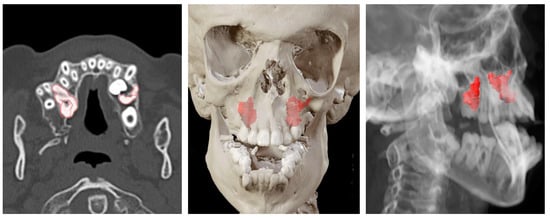

2. Materials and Methods

3. Results